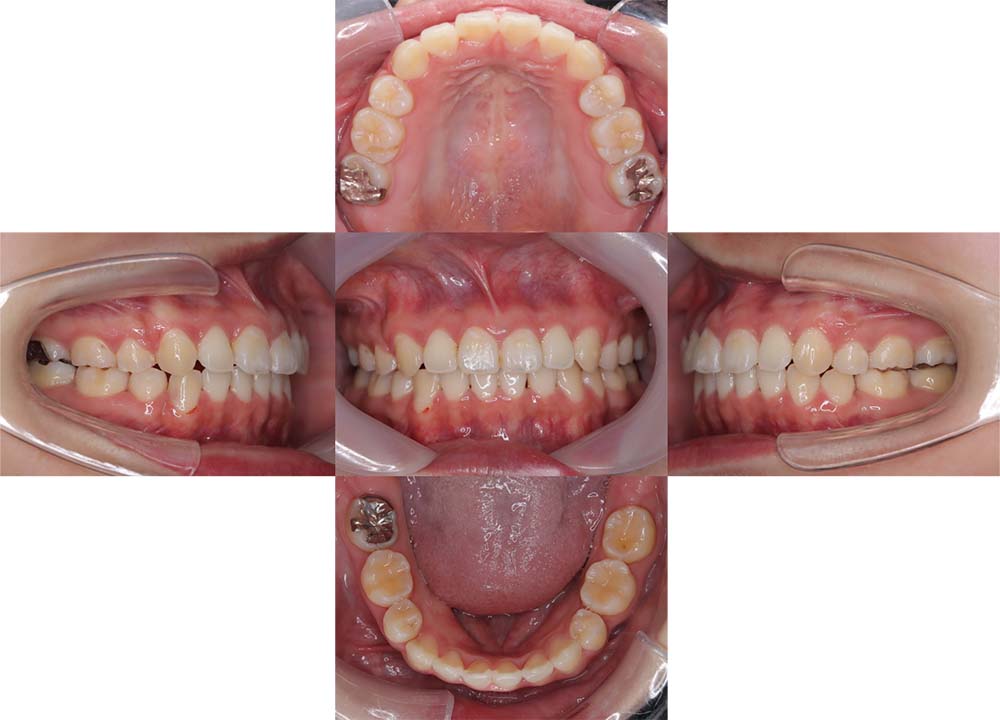

症例01

| 主訴 | 歯並びがガタガタしている。 |

| 診断名あるいは主な症状 | 叢生 |

| 年齢/性別 | 22歳・男性 |

| 矯正ステージ | 大人の矯正治療 |

| 治療方法 | ワイヤー矯正 |

| 抜歯部位/抜歯有無 | 非抜歯 |

| 治療内容 | 上顎大臼歯の遠心移動により前歯のガタガタを排列スペースを獲得し全顎的な排列を行った。 |

| 費用 | 85万円程度(2025.10時点の料金となります。) ※矯正基本料金、審美ブラケットを含む |

| 治療期間 | 2年4ヶ月 |

| 主なリスク・副作用 | 痛み、歯根吸収、歯肉退縮、虫歯、後戻り |